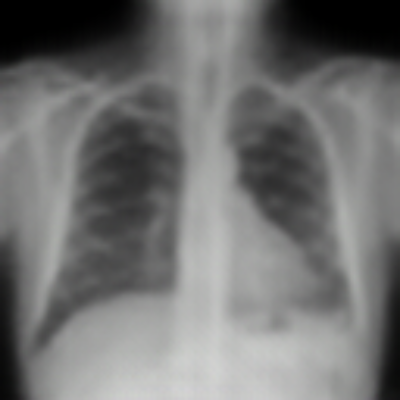

| Real-style X-rays | X2CTGAN | PerX2CT | DX2CT | ||

| PA | ![]() |

Coronal | ![]() |

![]() |

| Lateral | ![]() |

Sagittal | ![]() |

| Axial | ![]() |

The qualitative results in Figure 4 with real-world biplanar X-rays show that the structure of organs in reconstructed CTs by DX2CT better resembles to that of X-rays and DX2CT reconstructs sharper results, compared to the SOTA methods.